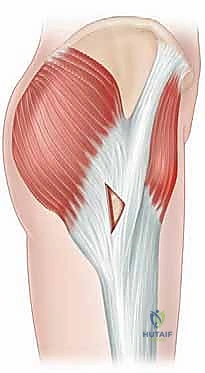

مركب العضلة الحرقفية القطنية: محرك الورك القوي

في سياق متلازمة الورك الطاطئ، تلعب العضلة الحرقفية القطنية (Iliopsoas Muscle Complex) دور البطولة. تُعد هذه العضلة من أقوى عضلات ثني الورك (Hip Flexors) في الجسم، وهي المسؤولة عن رفع ركبتك نحو صدرك. تتكون هذه البنية من عضلتين رئيسيتين تندمجان معًا:

تتحد ألياف هاتين العضلتين لتشكيل وتر واحد سميك وقوي ينزل نحو الفخذ. يمر هذا الوتر فوق بروز عظمي في الحوض يُسمى "البروز العاني الحرقفي" (Iliopectineal Eminence) وحافة مفصل الورك الأمامية، قبل أن ينغرس بقوة في المدور الصغير (Lesser Trochanter) لعظم الفخذ. هذا المسار التشريحي الذي يتضمن انحناءً حادًا للوتر فوق البروز العظمي هو العامل الميكانيكي الرئيسي في حدوث "الطقطقة الداخلية".

يحدث هذا النوع على الجانب الخارجي (الوحشي) من الورك. ينجم عن انزلاق شريط من الأنسجة الضامة القوية يُسمى "الشريط الحرقفي الظنبوبي" (Iliotibial Band - ITB)، أو أحيانًا الحافة الأمامية للعضلة الألوية الكبرى (Gluteus Maximus)، فوق بروز عظمي كبير في أعلى عظم الفخذ يُسمى "المدور الكبير" (Greater Trochanter).